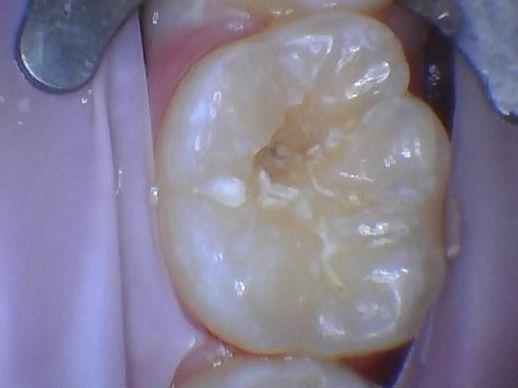

This case shows the progression of a cavity being filled. The first photo shows the beginning of the cavity removal followed by a photo that shows the dye used during cavity removal.